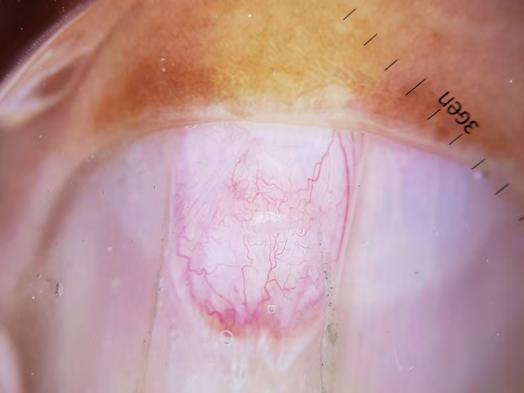

Decisão final: 27/02/2025

Como citar este artigo:

Santos SNMB, Kobata SI, Morato IB, Sobreira NP. Onicomatricoma: sempre um desafio diagnóstico. Surg Cosmet Dermatol. 2025;17:e20250408.

INTRODUÇÃO

O onicomatricoma (OM) é um tumor raro e benigno do complexo ungueal, de origem ainda incerta, que ocorre principalmente na matriz ungueal dos dedos das mãos. A apresentação clínica clássica inclui faixa amarelada espessa na lâmina ungueal, com tendência à hipercurvatura transversa, e frequentemente são observados os achados de hemorragia em estilhaço e cavitações na porção distal da lâmina ungueal.1-3 Em geral assintomático e raramente associado a paroníquia crônica, o OM pode podendo ocasionar dor importante e prejuízo na qualidade de vida.2 Na literatura, encontramos vários relatos de um longo percurso assistencial de pacientes até o devido diagnóstico e tratamento adequado.4,5 Este artigo relata um caso clínico referenciado ao serviço de dermatologia tratado por anos como onicomicose, cujo diagnóstico clínico e histopatológico foi compatível com OM. São discutidos a seguir critérios clínicos e complementares para um diagnóstico mais precoce e assertivo.

RELATO DE CASO